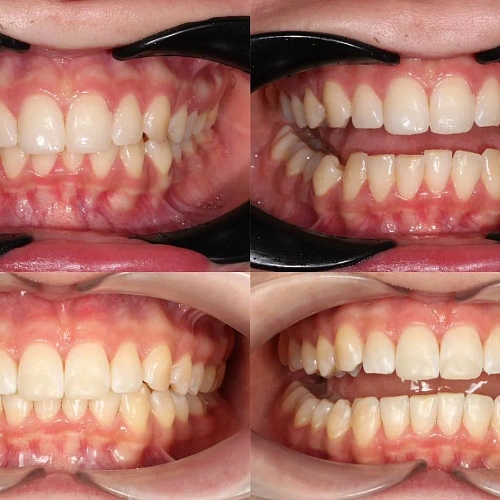

Зубы выровнены, скученность устранена, линия смыкания нормализована. Установлены несъёмные ретейнеры на обе челюсти, сняты слепки для ретенционных кап.

Я живу не в России, поэтому прилетать часто не получалось. Врач это учла и выстроила лечение так, чтобы между визитами проходило больше времени. Дозаказов было три — каждый раз ждала новые капы и начинала заново. Это растягивает процесс, но я понимала, что мой случай непростой. Зато на ретенцию прилетела и увидела финальный результат — зубы ровные, кайф.

Сложный случай: скученность на обеих челюстях плюс деформация кривой Шпее — жевательные зубы на разной высоте. Дополнительный вызов — пациентка живёт за рубежом, визиты реже, контроль сложнее. Три дозаказа — много, но каждый был обоснован: основной набор расширил дуги и убрал основную скученность, дозаказы последовательно довели смыкание до нормы. 82 капы за 30 месяцев — результат получен.